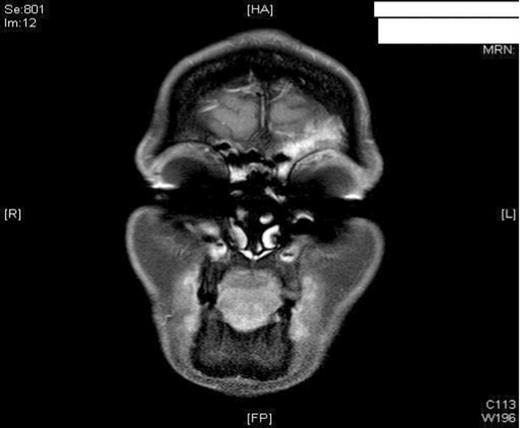

A 47-year old female smoker presented to the ENT department with worsening pain and progressive swelling to her left peri-orbital region and eyelid. On clinical examination the patient was acutely unwell. Rhinoscopy revealed mucopus draining from the left middle meatus. CT scanning revealed severe sinus disease in both frontal sinuses, with the left frontal sinus being expanded suggesting the presence of a mucocele (Figure 1). Both Frontonasal recesses and osteomeatal complexes were seen to be occupied by material bilaterally. Following Opthalmological review, she was managed initially with intravenous antibiotics and systemic steroids as well as intranasal steroids, decongestants and antimicrobial eye ointment. However, due to failure in resolution of symptoms, she was listed for surgical drainage of the mucocele using balloon sinuplasty.

The patient had an uneventful post-operative period and remained pain-free with no residual swelling of the forehead. She was discharged home 24 hours post-operatively with FlixonaseTM Nasules for 6 weeks, SterimarTM spray for 2 months and regular steam inhalations. At 6 months post-op, the patient remained asymptomatic and well. To avoid any unnecessary radiation, the patient was assessed with MRI imaging. As shown, the imaging revealed no complications and showed adequate resolution of the mucocele (Figure 3).

MRI imaging (a) coronal (b) axial views post procedure revealing resolution of the mucocele and no intracranial or orbital complications (see figure 1).